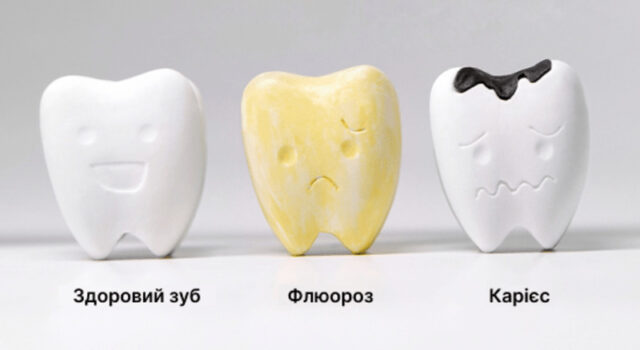

Пігментні плями – зміна кольору зубної емалі. Зазвичай вони не впливають на захисні властивості покриття зуба, але іноді можуть свідчити про початок захворювання. Карієс являє собою демінералізацію та подальше розм’якшення емалі та дентину з утворенням порожнини.

- флюороз (надлишок фтору);

У місцевостях, де вода містить підвищену кількість фтору, у мешканців спостерігається флюороз, що зовні проявляється появою темних плям на зубах. На початкових стадіях захворювання достатньо проведення професійного відбілювання із наступною ремінералізацією.